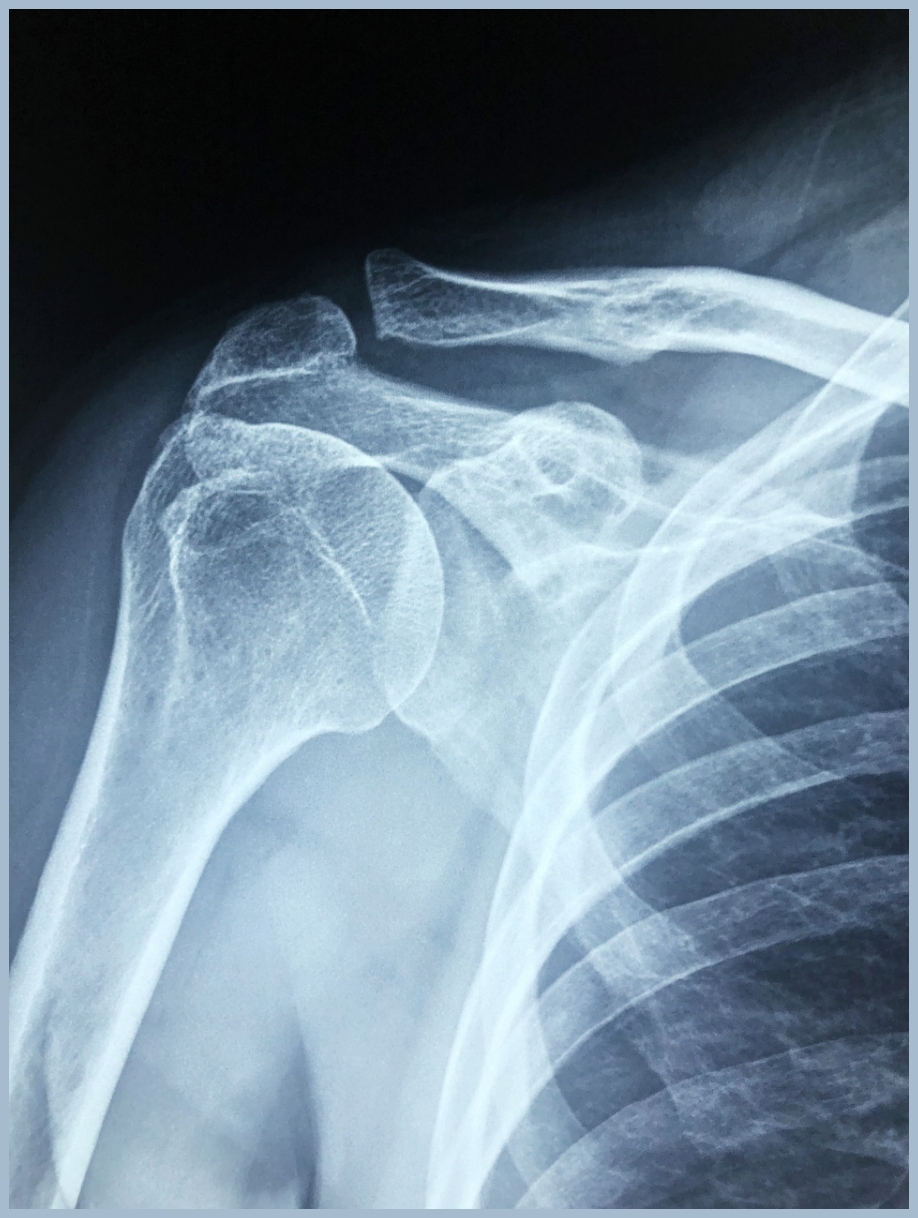

정확한 진단을 위해서는 먼저 자세한 병력 청취와 신체 검진이 필요합니다.

증상의 발생 시기와 양상을 파악하고, 통증 유발 동작을 확인하며, 근력 및 관절 가동 범위를 평가합니다.

이후 X-ray를 통해 골격 구조의 이상을 확인하고, MRI로 파열의 크기, 위치, 정도를 평가하며, 필요한 경우 초음파를 통한 실시간 동적 검사도 시행할 수 있습니다.